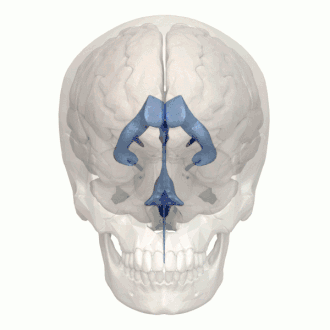

Ventricular system

In neuroanatomy, the ventricular system is a set of four interconnected cavities known as cerebral ventricles in the brain.[1][2] Within each ventricle is a region of choroid plexus which produces the circulating cerebrospinal fluid (CSF). The ventricular system is continuous with the central canal of the spinal cord from the fourth ventricle,[3] allowing for the flow of CSF to circulate.[3][4]

The system comprises four ventricles:[5]

- lateral ventricles right and left (one for each hemisphere)

- third ventricle

- fourth ventricle

There are several foramina, openings acting as channels, that connect the ventricles. The interventricular foramina (also called the foramina of Monro) connect the lateral ventricles to the third ventricle through which the cerebrospinal fluid can flow.

| interventricular foramina (Monro) | lateral ventricles | third ventricle |

| Cerebral aqueduct (Sylvius) | third ventricle | fourth ventricle |

| Median aperture (Magendie) | fourth ventricle | subarachnoid space via the cisterna magna |

| Right and left lateral apertures (Luschka) | fourth ventricle | subarachnoid space via the cistern of great cerebral vein |

Ventricles

The four cavities of the human brain are called ventricles.[6] The two largest are the lateral ventricles in the cerebrum, the third ventricle is in the diencephalon of the forebrain between the right and left thalamus, and the fourth ventricle is located at the back of the pons and upper half of the medulla oblongata of the hindbrain. The ventricles are concerned with the production and circulation of cerebrospinal fluid.[7]